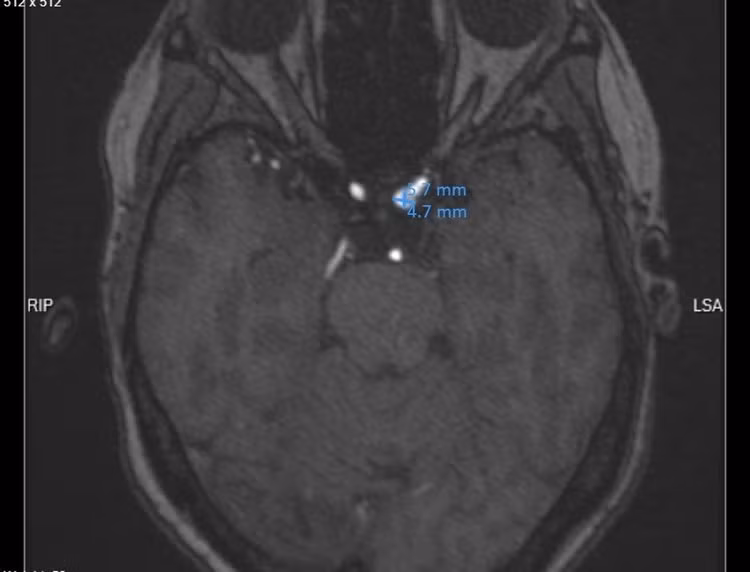

Qua thăm khám lâm sàng, các bác sĩ đã chỉ định chụp cộng hưởng từ mạch máu não. Kết quả ghi nhận bệnh nhân có túi phình mạch tại đoạn siphon của động mạch cảnh trong trái, kích thước khoảng 5 - 6 mm, thuộc nhóm túi phình mạch não kích thước trung bình.

phinh-mach-nao.jpg

Túi phình mạch máu não trên phim chụp - Ảnh BVCC